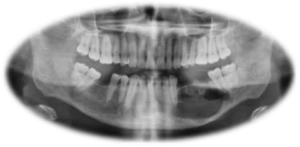

Benign cyst and tumor of jaws are prevalent in India and its number are increasing due to lack of oral health awareness. This Silent problems appear gigantic in size when it appears symptomatic. Often people lose its face due to their negligence towards surgical treatment. Only Surgical treatment can bring back the usual format of face. It comes under the expertise of Maxillofacial Surgeons.